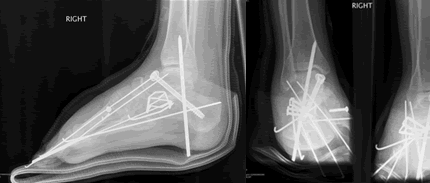

At 28 and already having sixteen surgical procedures behind me, life was not going as I had planned. I had left three jobs in the last year, one which I really loved, all because of the severe foot pain that I lived with everyday. The cause of the pain made a solution especially difficult. I had a congenital neuropathy called, Charcot Marie Tooth Disease, and a bone disease known as, Osteogenesis Imperfecta, along with many serious injuries over the past ten years making mine an especially complicated case. My body felt much older than it's young looks betrayed.

I was referred to Doctor Leavitt at the very beginning of 2008. When I met Dr. Leavitt for the first time I left knowing two things. First, my case would be difficult and even impossible for most surgeons (in fact many doctor's in the past refused to operate on me because of the complicated nature of my case). Second, Dr. Leavitt was the right man. I've never left a consultation feeling both so overwhelmed at what was in store for me in terms of pain, recovery, and rehab and yet so at ease that I was in the most capable hands. To say Dr. Leavitt is thorough would be an understatement. In fact, I had four visits in the month leading up to my surgery and I even received a phone call on a Sunday afternoon from Dr. Leavitt to confirm something he was working on at home. I took comfort knowing that I was going into a situation that had been planned out down to every detail and every contingency was accounted for. Simply put, Doctor Leavitt is the most accessible and capable doctor I have ever met.

Surgery was completed March 6th and now, all things considered, I feel great. Dr. Leavitt is simply amazed at how quickly I am healing and I am amazed at how quickly my foot is starting to feel more like a normal foot should. Everybody knows doctors save lives but rarely do we think of podiatrists as the same type of glorified life-saving doctors American television and cinema makes into the ultimate heroes everyday. But Dr. Leavitt saves lives. Maybe you can't quite understand that until your feet hurt everyday all day long or until the dream job you've wanted is just out of grasp because of a congenital foot abnormality. But, if like me, and hundreds of others whom he has helped, you have these types of problems that no other doctor can fix-then you do understand. Doctor Leavitt changes lives and he saves lives.